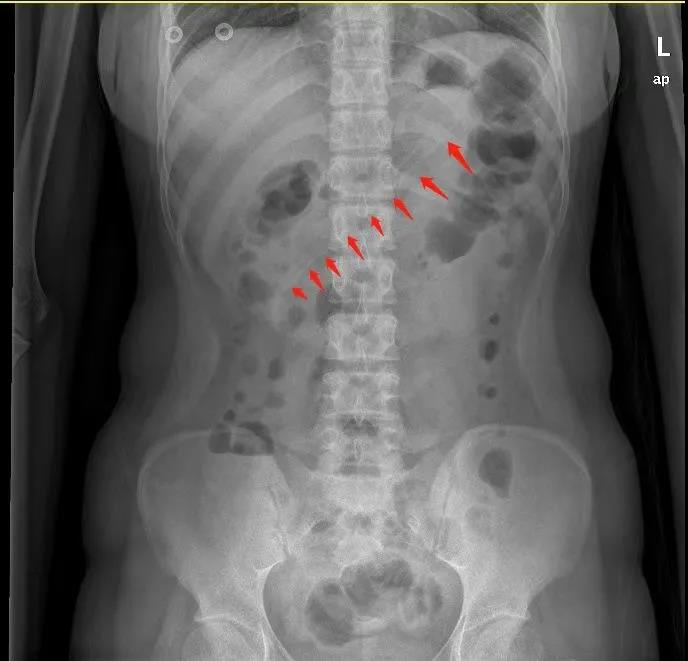

李小姐去东莞石碣医院求助医生,腹部X线检查显示,李小姐胃中的勺子长达17厘米。如果不取出,患者可能会出现消化道梗阻、出血和穿孔等并发症。医生赶紧安排李小姐入院治疗。

实施无痛麻醉后,在医生操作下,胃镜快速就位。通过胃镜,一进入胃腔就能看到一根长长的塑料勺子横跨在胃体至十二指肠球部。